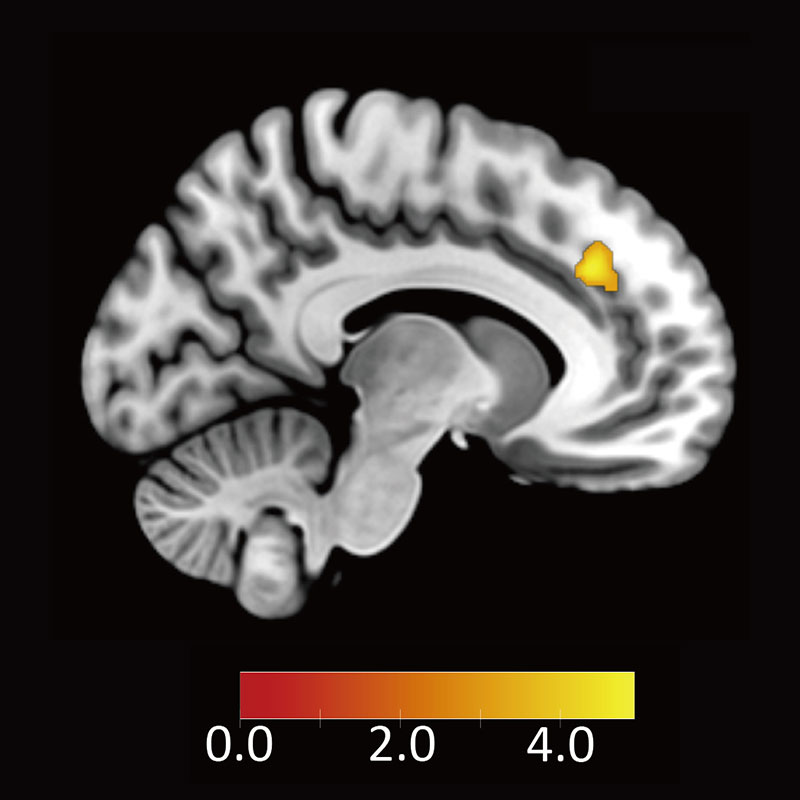

情報通信研究機構(NICT)未来ICT研究所 脳情報通信融合研究センター(CiNet)沼野正太郎協力研究員、春野雅彦室長の研究グループは、交渉の場面でヒトが不公平な提案を受け入れるとき、脳の背側前帯状皮質が、不公平によって生じる感情を抑えることで不公平な提案を受け入れるという脳内メカニズムを見出した。

今回、63名の参加者を対象にfMRI実験を行い、解析したところ、背側前帯状皮質が、腹外側前頭前野を介して、不公平によって生じる感情を抑えることがわかった。

その結果、背側前帯状皮質が見つかった。

次に、不公平な条件が提示されたときに、この背側前帯状皮質が抑制的に働くと考えられる脳領域、すなわち負の結合度を示す領域を探索したところ、腹外側前頭前野が見つかった。

さらに、背側前帯状皮質と腹外側前頭前野の結合度から、各参加者が不公平な提案を受け入れる割合と、反応時間の両方を予測できることがわかった。